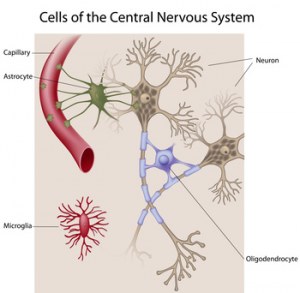

Células primárias do cérebro humano adulto normal

Diferentes células cerebrais, tais como neurónios, astrócitos, oligendrócitos... bem como meios específicos para estas células e biológicos destes tipos de células.